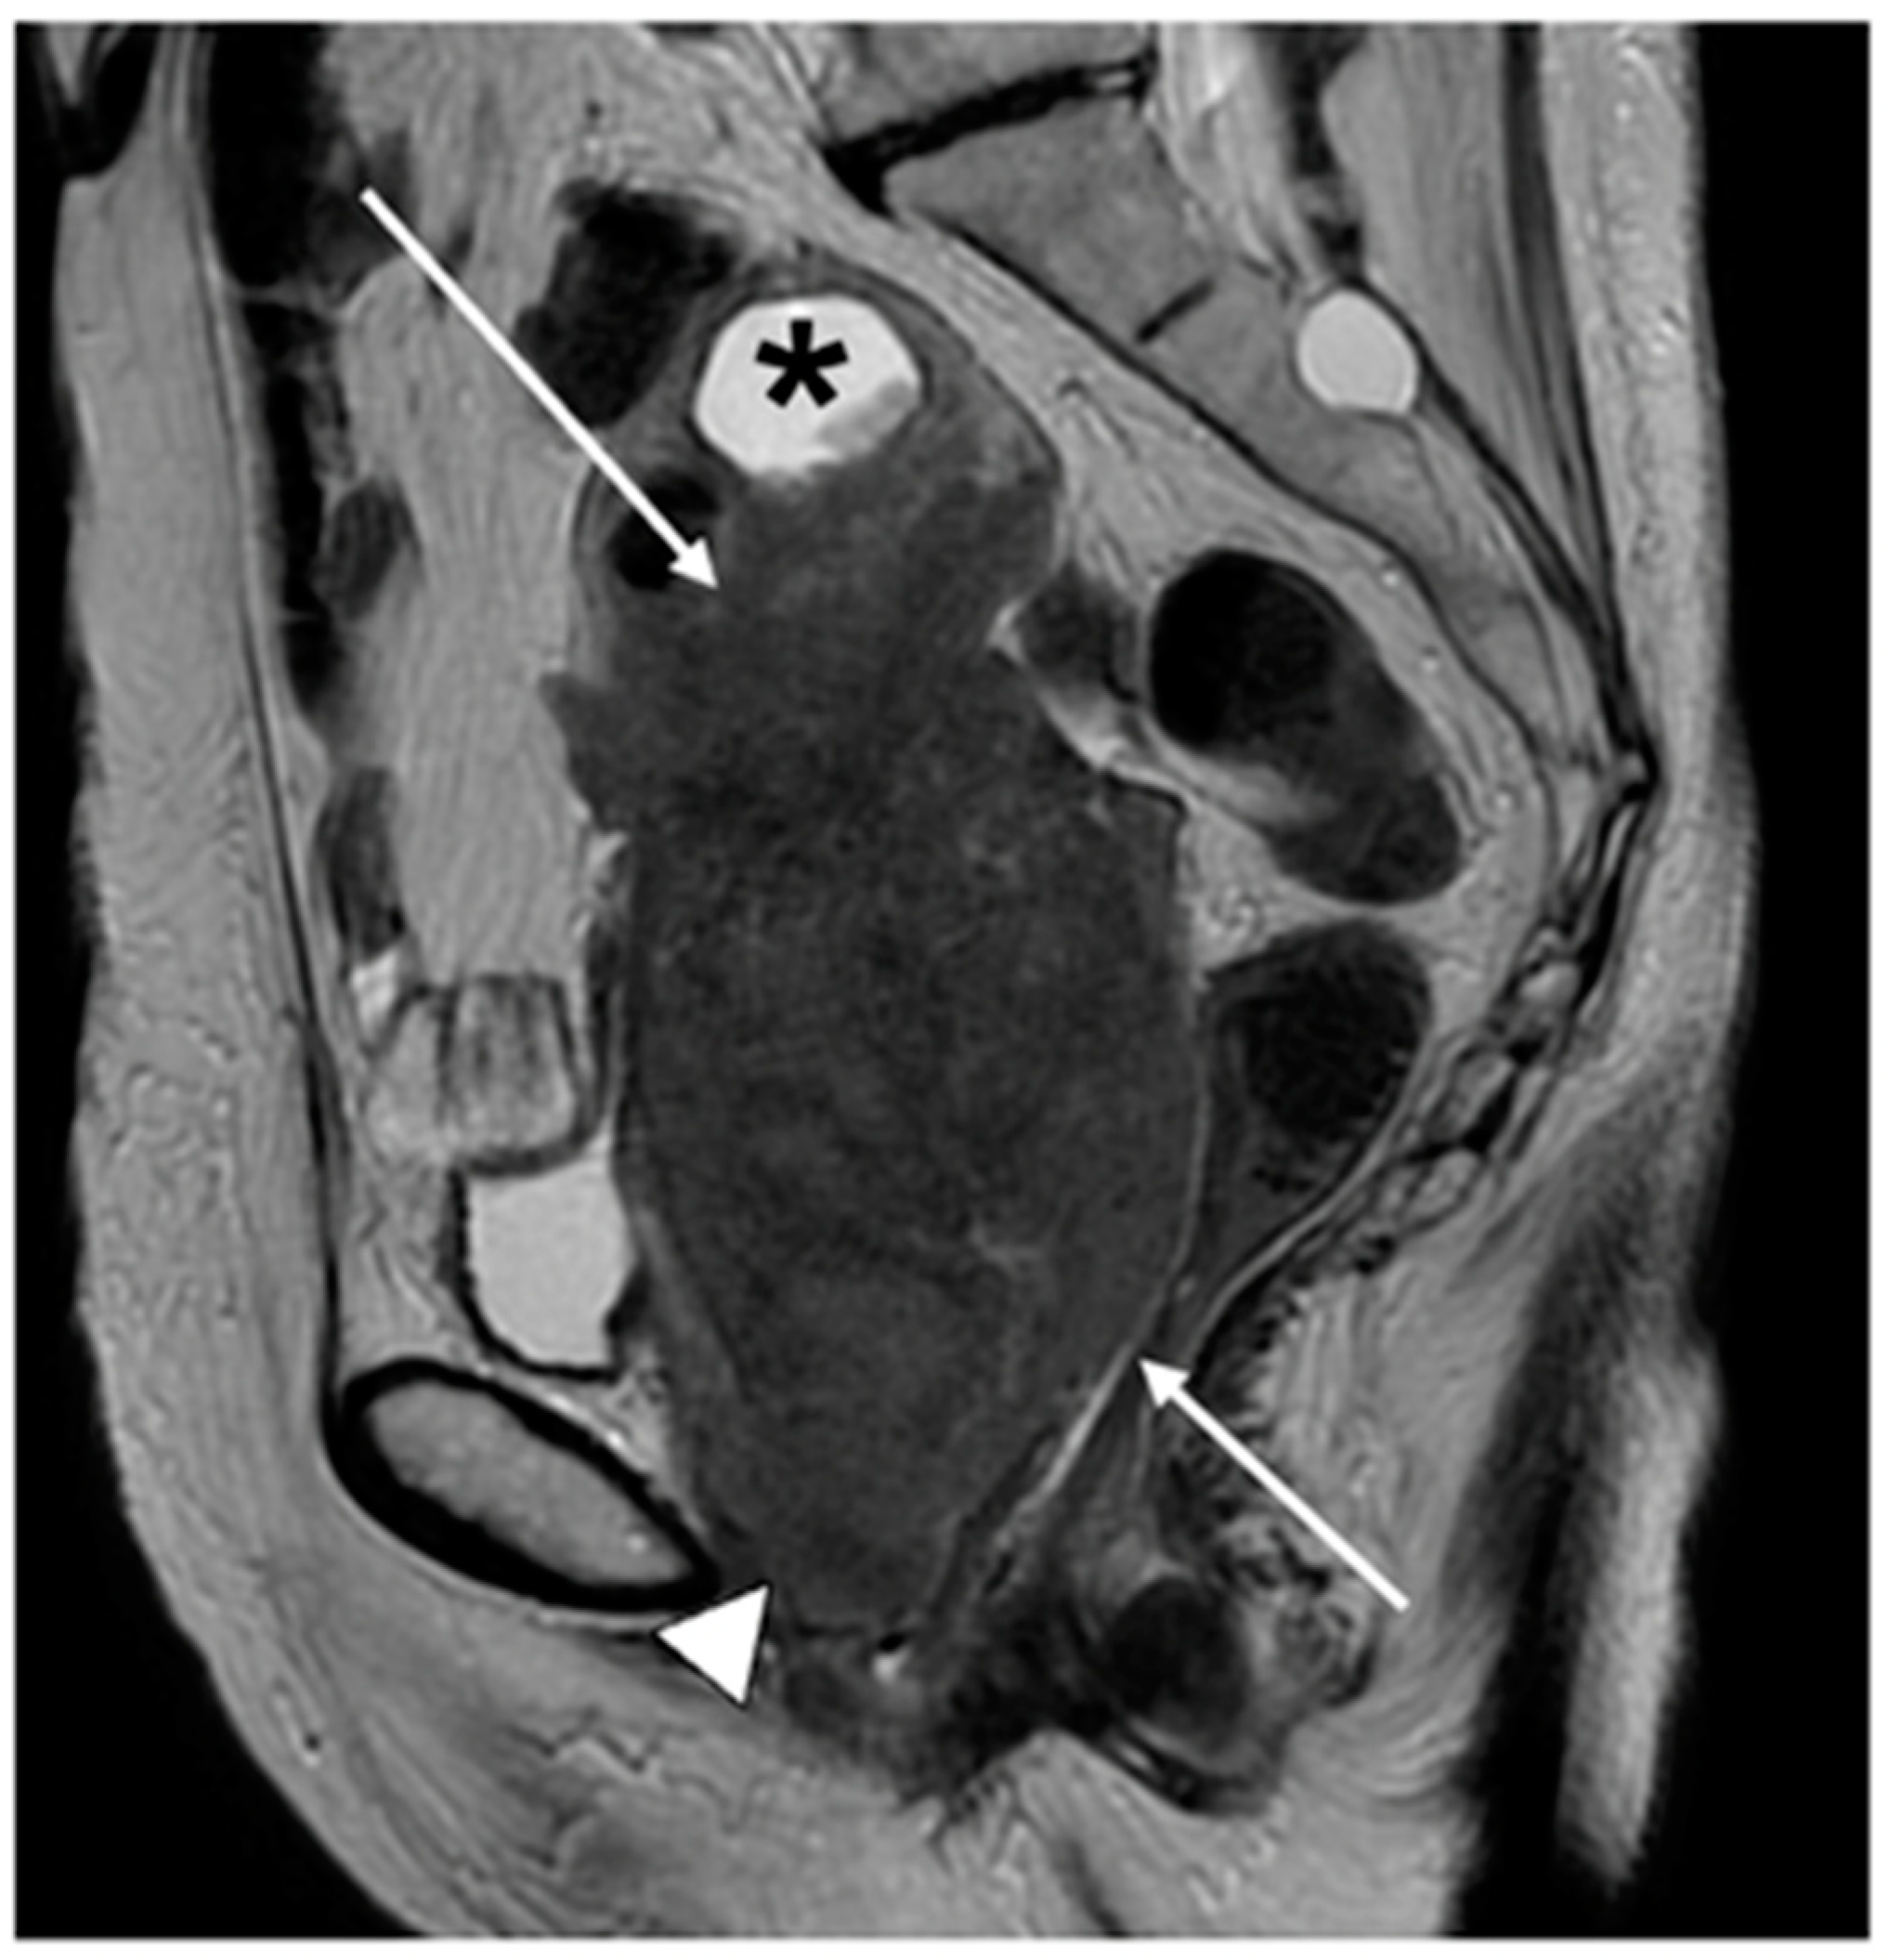

| Stage IV | Spread to adjacent and distant organs |

| IVA | Rectal or bladder involvement |